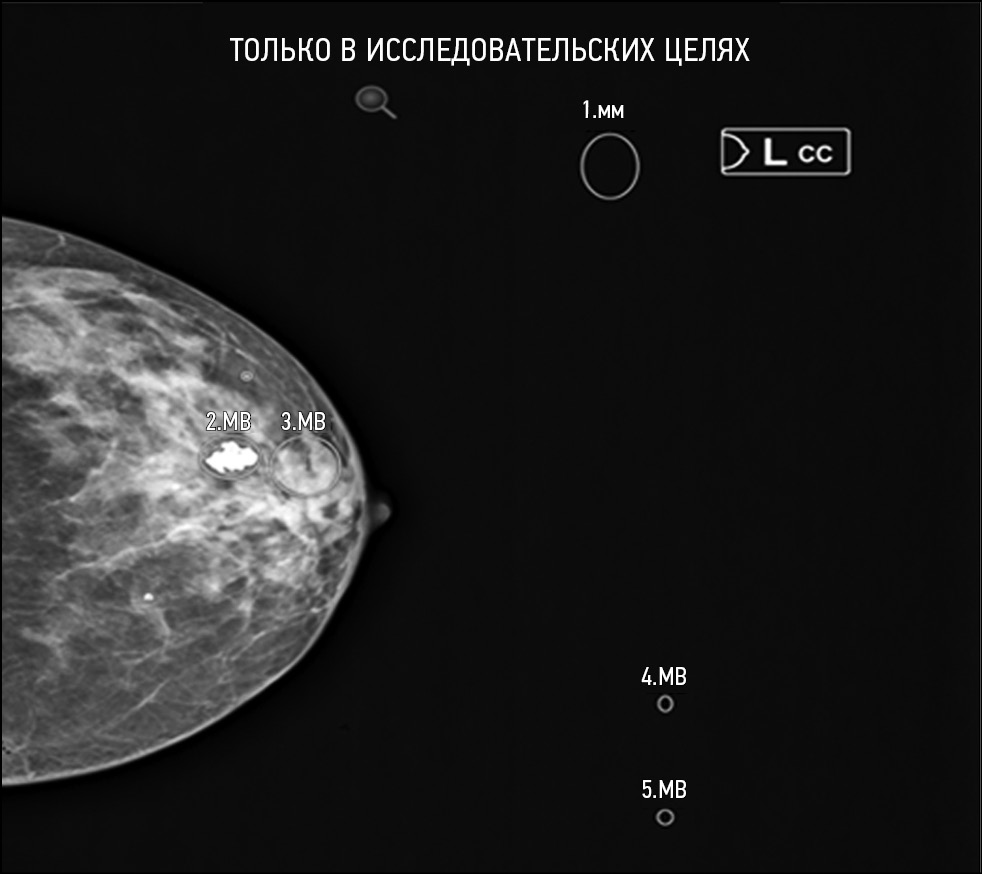

Fig. 3. Defect: not all necessary images have been evaluated. Modality: mammography.

Fig. 4. Defect: off-target markings; Modality: mammography.

- Defects that affect the safety of patients and work of HCPs: failure to implement functions declared by the manufacturer; comments that influence a radiologist or complicate their work; and irreversible damage to original research data. This group includes, for example, Group D (D2, D3, D4) and F defects. Separately, a D7 defect (absence of a warning label “For research/scientific use only”) should be considered. This defect can only occur in the research setting and can never occur when using AI-based software as a medical device.

- Defects that do not affect the safety of patients but affect the work of HCPs: functional defects that do not conform to generally accepted standards for the presentation of research interpretation results. This group includes Group E and C (C1, C2, C3) defects.